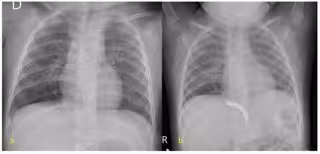

La Fundación Jiménez Díaz ha tratado con éxito un secuestro pulmonar en una paciente de 19 meses mediante embolización, como alternativa a la cirugía clásica. Se trata de una malformación congénita, que sufre entre el 0,15 y el 1,8 por ciento de la población general, puede producir infecciones de repetición y, en los casos más graves, hemoptisis o hemorragias pulmonares, hipertensión pulmonar, insuficiencia cardíaca congestiva severa e incluso fallo cardíaco.

Según ha informado la FJD en un comunicado, la embolización de los vasos sistémicos en los secuestros pulmonares se presenta en la actualidad "como una alternativa terapéutica factible, y un recurso a tener en cuenta en casos seleccionados, que puede incluso constituir la primera línea de tratamiento en centros experimentados, frente a la lobectomía pulmonar con resección del lóbulo pulmonar afecto, tratamiento de elección hasta el momento".

Y es que, al tratarse de una técnica menos invasiva que la intervención quirúrgica clásica, entre los beneficios de la embolización destacan la reducción de riesgos operatorios y complicaciones postoperatorias, la disminución del tiempo de hospitalización, la ausencia de cicatriz postquirúrgica y el hecho de que evita la aparición de la escoliosis y pectus excavatum asociados a las toracotomías. "Se han descrito incluso involuciones totales de las lesiones parenquimatosas tras la embolización", ha asevera el doctor Crespo.